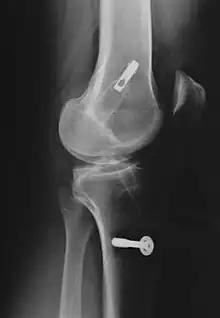

![]() Arthroscopic anterior cruciate ligament (ACL) reconstruction (right knee). The tendon of the semitendinosus muscle was prelevated, folded and used as an autograft (1). It appears through the remnant of the injured original ACL (3). The autograft then courses upwardly and backwardly in front of the posterior cruciate ligament (2). | |